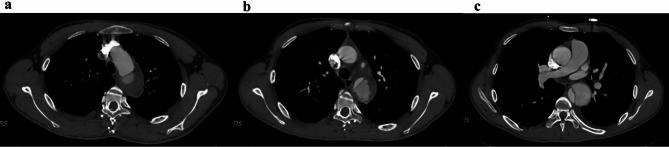

Case report: A young male patient presented with acute chest pain following strenuous exertion. Initial outpatient evaluation, including complete blood count (CBC), liver function tests (LFTs), renal function tests (RFTs), cardiac enzymes, and chest X-ray (CXR), yielded nondiagnostic results, leading to his discharge with analgesics. Three days later, during a national holiday when outpatient clinics were closed, the patient returned to the emergency department (ED) with persistent chest pain. A meticulous review of the initial CXR by the emergency physician revealed mediastinal widening (measuring 8.5 cm) and an abnormal contour of the aorta. Subsequent emergency computed tomography angiography (CTA) confirmed the diagnosis of a Stanford type B aortic dissection.